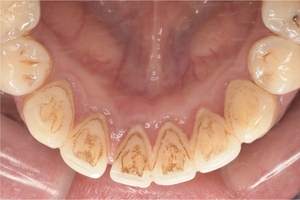

CASE 3

Before

After

基本情報

| 年齢・性別 | 30代・女性 |

|---|---|

| 主訴 | 定期検診 |

| 治療内容 | PMTC |

| 治療期間 | 60分 |

| 治療費 | 5,750円 |

| リスク・副作用 | しみる可能性があります。 |

| 治療方針 | PMTCでステインの除去。 |

| 担当者所見 | ステインが付きやすいため、3カ月毎の定期検診で除去する。 |